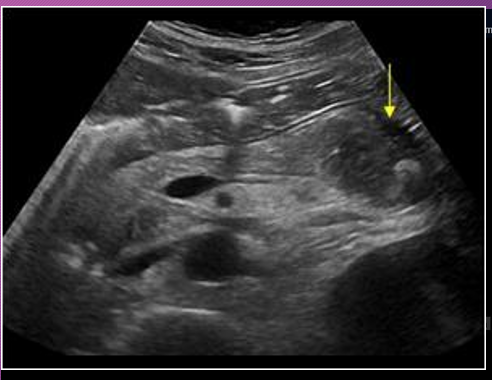

Sonographically, pseudocysts appear as ____-_____ masses, _______ with increase through _______

well-defined; anechoic; transmission

______ seen within the pseudocyst may occur from complications of ______ or _______

Debris; infection; hemorrhage

Borders of pseudocysts are very _______, and they usually are _____ than other simple cysts. ________ may develop _____ the walls of the pseudocyst

echogenic; thicker; Calcification; within

A ______ is a collection of fluid that arises from the loculation of ________ processes, _______, or _______

pseudocyst; inflammatory; necrosis; hemorrhage

A pancreatic ______ is a ___-filled mass that develops ______ of the pancreas

pseudocyst; fluid; outside

The most common location of a pseudocyst is in the ______ sac ______ to the _______ and ______ to the _______

lesser; anterior; pancreas; posterior; stomach